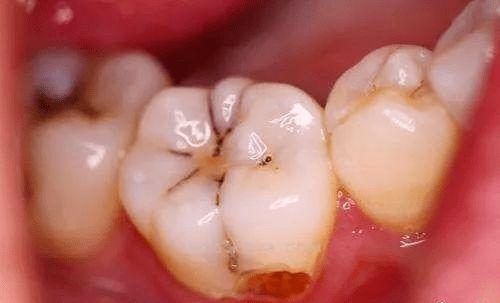

牙齒表面的小黑點(diǎn)或黑線

這是較為常見的早期癥狀之一。小黑點(diǎn)或黑線可能是細(xì)菌產(chǎn)生的色素沉著,也可能是齲壞的開始。如果用探針探查,會(huì)發(fā)現(xiàn)質(zhì)地變軟。臨床觀察發(fā)現(xiàn),約50%的早期齲齒會(huì)先出現(xiàn)小黑點(diǎn)或黑線。